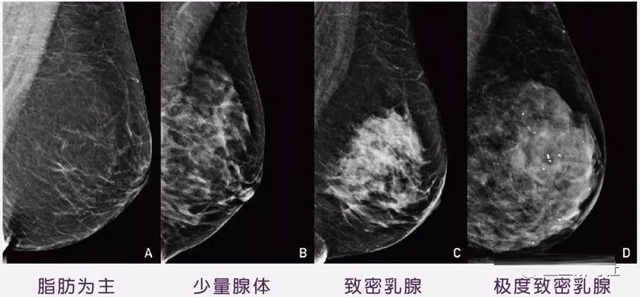

女性乳腺的自我檢查,特別是注意有小結(jié)節(jié),腫塊,乳頭有液體滲出情況,需要通過乳腺DR,X光線,磁共振等影像技術(shù)檢查。胸的大小跟乳腺癌沒多大關(guān)系,乳腺的密度大發(fā)病率高一些,胸小脂肪少致密性大。更容易乳腺癌。這個還不能通過自我檢查來確認(rèn)。致密乳腺組織看上去是白色或淺灰色需要通過乳腺X射線檢查。